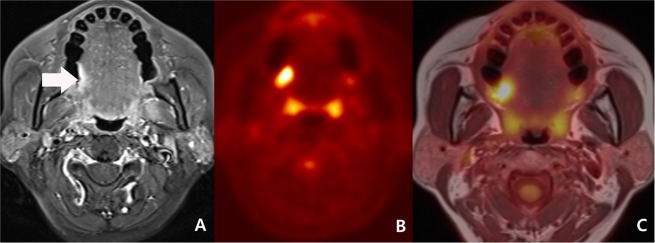

In concordant cases, PET/MRI had a sensitivity of 87.3%, a specificity of 91.7%, a PPV of 93.2%, a NPV of 84.6%, and an accuracy of 89.2%. (Fig. 1)

Figure 1.

Initial work-up of a 53-year-old woman with right tongue cancer (malignant concordant diagnosis) and bilateral cervical metastasis (benign concordant diagnosis). (A) A transverse fat-suppression contrast enhanced MRI revealed an enhancing lesion at right posterolateral tongue (arrow). A neuroradiologist scored the lesion as 4 (probably malignant). (B) As PET reveals hypermetabolism (maximal SUV: 9.4) at the corresponding area, a nuclear medicine specialist scored the lesion as 5 (definitely malignant). (C) A consensus score of PET/MRI was 5 (definitely malignant). Right tongue lesion was surgically proved to be squamous cell carcinoma. In addition, there were numerous tiny lymph node metastases proven by surgical specimens of right neck dissection, although imaging with PET, MRI, and PET/MRI could not detect them.

While NPV was not statistically different between benign concordant cases (84.6%, 44/52) and discordant cases (86.7%, 13/15), PPV was larger in malignant concordant cases (93.2%, 55/59) than in discordant cases (62.5%, 5/8) (p = 0.0404) (Figs. 1, 2).